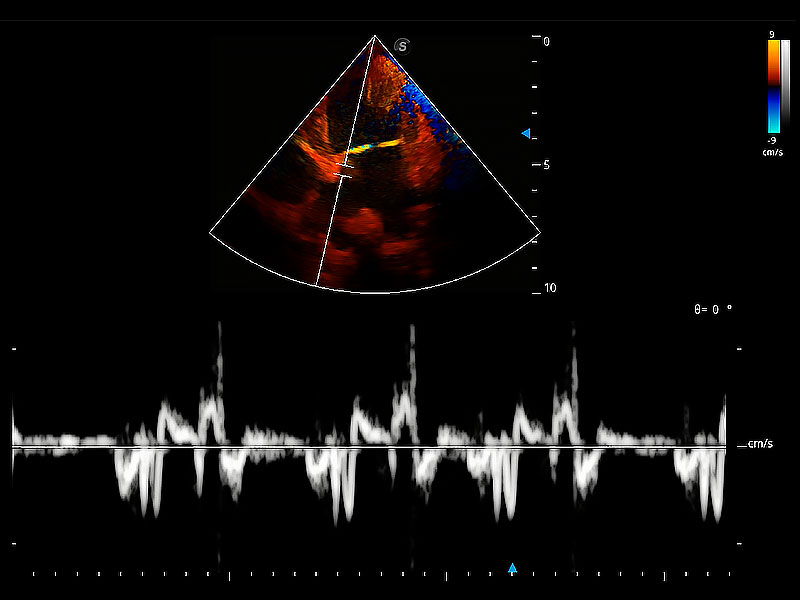

隨著取樣門位置改變,頻譜多普勒包絡(luò)可進(jìn)行自動眼蹤測量,且可自由配置測量的參數(shù)。